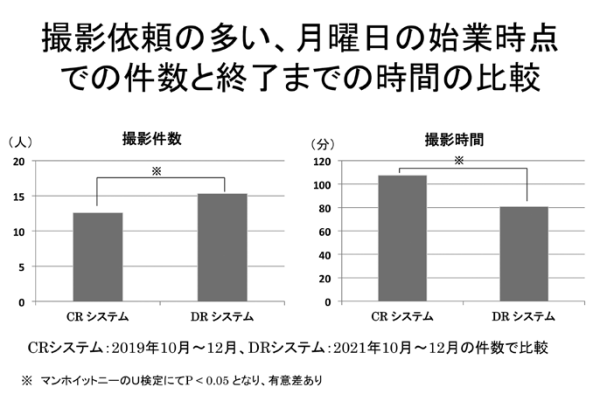

そこで両者の撮影件数とそれに要する撮影時間の比較を行った。病棟患者さんのX線ポータブル撮影の依頼の多い月曜日の朝にRISにオーダーされた患者さんの撮影件数とその撮影が完了するまでの時間を調べた。対象期間は、CRシステムは、2019年10月から12月の月曜日で、DRシステムは、2021年10月から12月の月曜日のそれぞれ3ヶ月間とした。比較した項目は、8時30分時点のX線ポータブル撮影の依頼件数と撮影が実施完了までの時間をRISと画像の実施時刻から調べた。その結果は、CRシステムは、平均12.6±3.0件で、検査終了まで平均107.4±25.1分であった。

DRシステムは、平均15.3±3.4件で、検査終了まで平均80.8±35.5分であった。両社の比較で明らかになったことは、DRシステムでは、CRシステムに比べて撮影件数が増えても撮影完了までの時間が短縮され、検査効率が向上した(図3)。